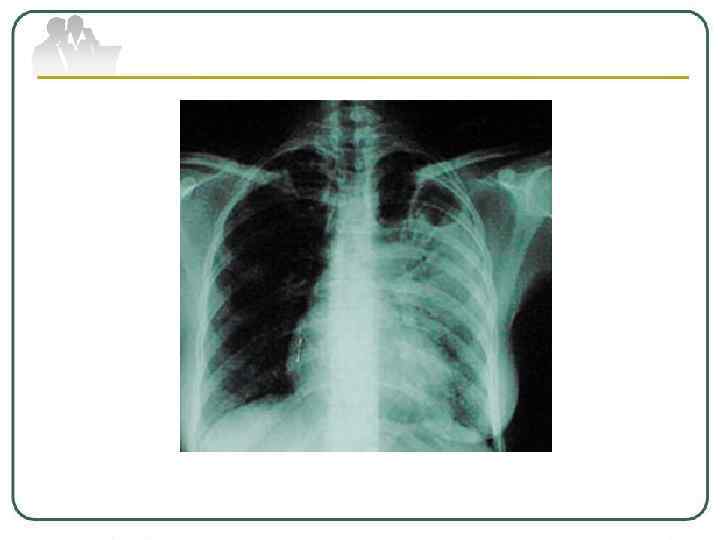

Туберкулема легких - понятие, объединяющее разнообразные по генезу инкапсулированные казеозные фокусы величиной более 1, 0 см в диаметре. Различают туберкулемы иифильтративно-пневмонического типа, гомогенные, слоистые, конгломератные и так называемые "псевдотуберкулемы" - заполненные каверны. На рентгенограмме туберкулемы выявляются в виде тени округлой формы с четкими контурами. В фокусе может определяться серповидное просветление за счет распада, иногда перифокальное воспаление и небольшое количество бронхогенных очагов, а также участки обызвествления.